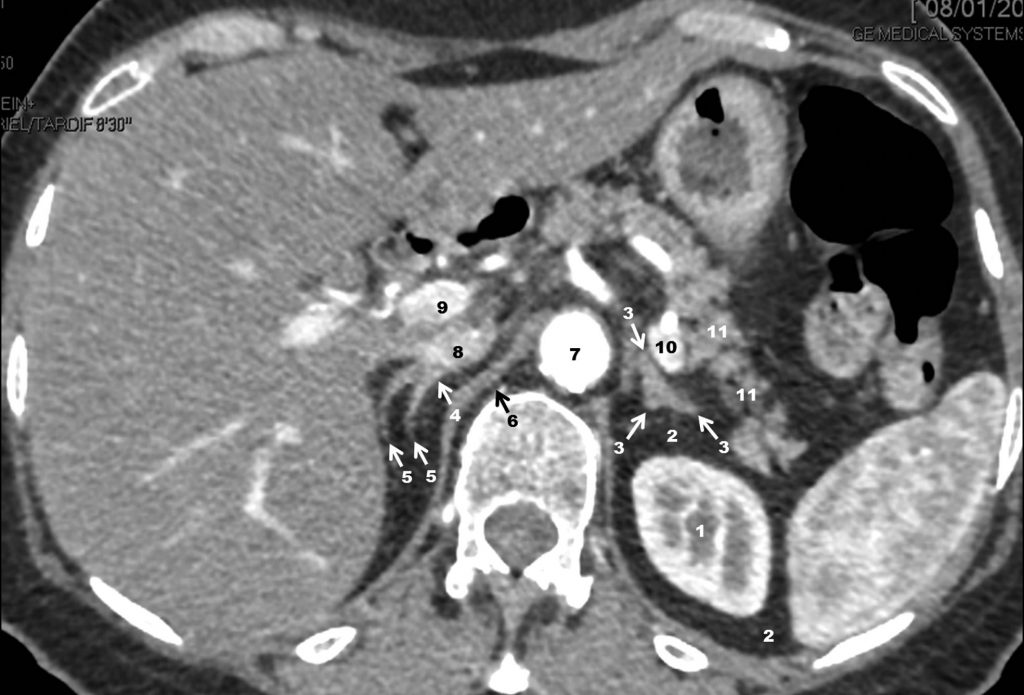

Fig. 19.10. Scanner rénal avec injection de produit de contraste à la phase artérielle (ou corticomédullaire) 40 secondes après injection. Coupe passant par le pôle supérieur du rein gauche et les glandes surrénales.

1. Rein gauche. 2. Graisse périrénale et inter-surrénalo-rénale. 3. Surrénale gauche. 4. Corps de la surrénale droite. 5. Bras interne et externe de la surrénale droite. 6. Pilier du diaphragme. 7. Aorte. 8. Veine cave inférieure. 9. Veine porte. 10. Veine splénique (au contact de l’artère splénique en avant). 11. Queue du pancréas.

Source : CERF, CNEBMN, 2022.